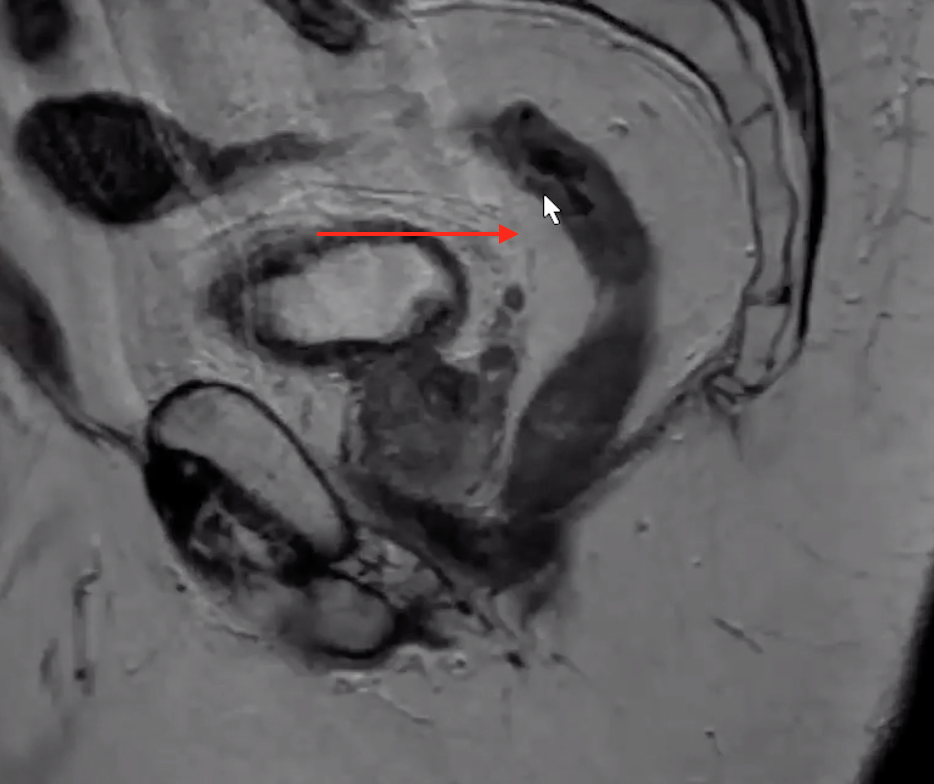

Rectal Wall

• Muscularis

• Darker external ring (blue)

• Mucosa

• The brighter/white internal stuff (red)

• Made up of the mucosa and submucosa but these cannot be differentiated on imaged they run together

Peritoneal Reflection

• Thin dark line that has a bend in it anterior to the rectum